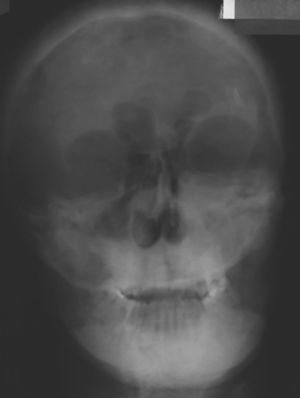

Caso clínicoPaciente, sexo masculino, 29 años de edad, derivado el año 2004 desde endocrinología al servicio de cirugía maxilofacial con diagnóstico de tumor maxilar en estudio. Sus antecedentes mórbidos incluyen insuficiencia renal crónica diagnosticada a los 18 años, en tratamiento con hemodiálisis 3 veces por semana. A los 27 años se detecta, en una ecotomografía doppler, la presencia de nódulos bilaterales compatibles con adenoma paratiroideo y niveles de PTH de 2.448pg/ml (150-500pg/ml). Con estos antecedentes se diagnosticó hiperparatiroidismo secundario. Se realiza la paratiroidectomía parcial y se indica tratamiento farmacológico protocolario, obteniéndose la normalización de los niveles séricos de calcio, pero manteniéndose altos los niveles de paratohormona. El paciente nota aumento de volumen en la zona maxilar izquierda, de crecimiento lento pero progresivo con 2 años de evolución, desde el año 2002. Al momento de consultar en nuestro servicio, clínicamente se observa aumento de volumen que compromete el maxilar superior izquierdo en su cara anterior, posterior y paladar duro, de consistencia firme, de 4cm de diámetro, indoloro, cubierto por piel y mucosa de aspecto normal, sin alteración sensitiva, que produce asimetría y deformación facial evidente (figs. 1 y 2). En los exámenes radiográficos se observan múltiples imágenes osteolíticas que afectan el cráneo, la mandíbula y el maxilar izquierdo (figs. 3 y 4). El TAC muestra tumoración exofítica que compromete maxilar izquierdo, seno maxilar, fosas nasales y piso de la órbita izquierda (fig. 5).

Se realizan controles postoperatorios clínicos y radiográficos, se evidencia clínicamente simetría facial, sin compromiso de sensibilidad y ausencia de recurrencia durante los 7 años desde la resección del tumor (figs. 9-13). (fig. 14)